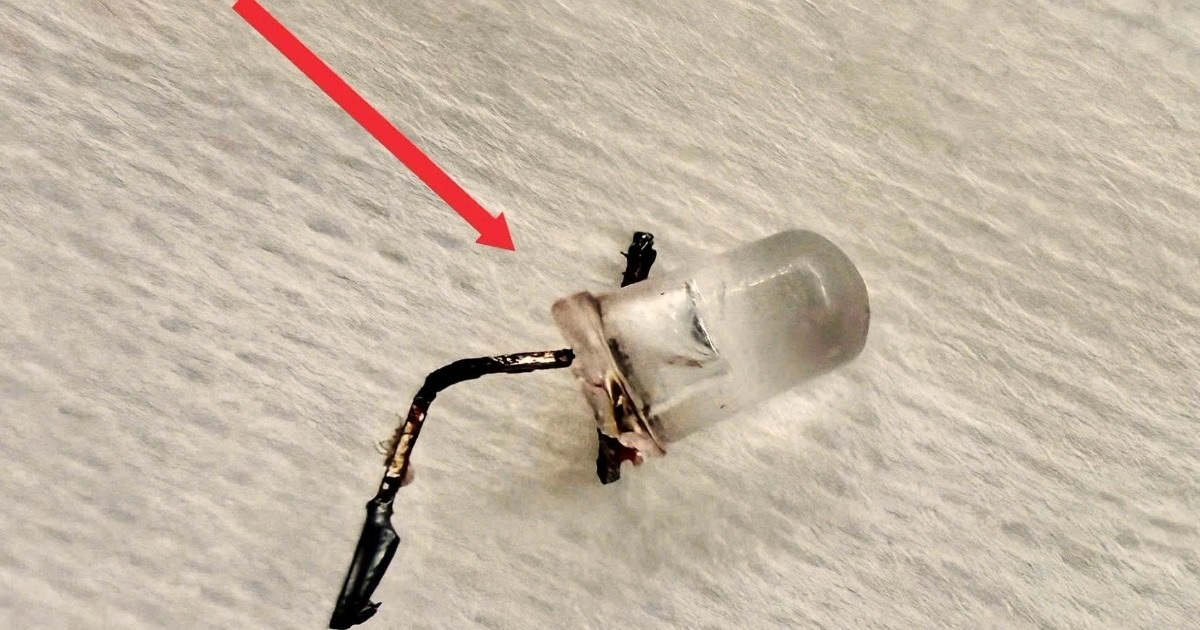

Dị vật nghi ngờ là một bóng đèn LED nằm sâu trong phế quản. Nhưng để lấy dị vật ra không hề dễ dàng. Khó khăn lớn nhất nằm ở cấu trúc của bóng đèn LED, vì phần đuôi đèn phình to và sắc nhọn, dễ mắc kẹt lúc kéo qua thanh quản, khiến nguy cơ gây trầy xước, rách niêm mạc hoặc kẹt lại ngay giữa 2 dây thanh là rất cao.

Đặc biệt, đường thở của cháu bé 9 tháng tuổi rất nhỏ, khó quan sát và thao tác. Bác sĩ buộc phải xoay chỉnh dị vật từng chút một và lựa hướng tối ưu để đưa phần đầu đèn ra trước, hạn chế tối đa tổn thương.

Bằng thao tác đúng chuyên môn, sự tỉ mỉ xoay trở từng milimet để lấy dị vật trong phế quản rất bé, cùng sự phối hợp chặt chẽ của đội ngũ y bác sĩ liên chuyên khoa, bóng đèn LED mắc kẹt cuối cùng đã được ê-kíp lấy ra an toàn khỏi cơ thể bệnh nhi.

Theo BSCKI Lý Phạm Hoàng Vinh, dị vật đường thở ở trẻ nhỏ luôn là cấp cứu nguy hiểm, đặc biệt với các vật có hình dạng bất thường như bóng đèn LED. Không chỉ gây tắc nghẽn, những dị vật này còn có thể gây trầy xước, thủng đường thở hoặc dẫn đến các biến chứng nặng nề nếu xử trí không đúng cách.